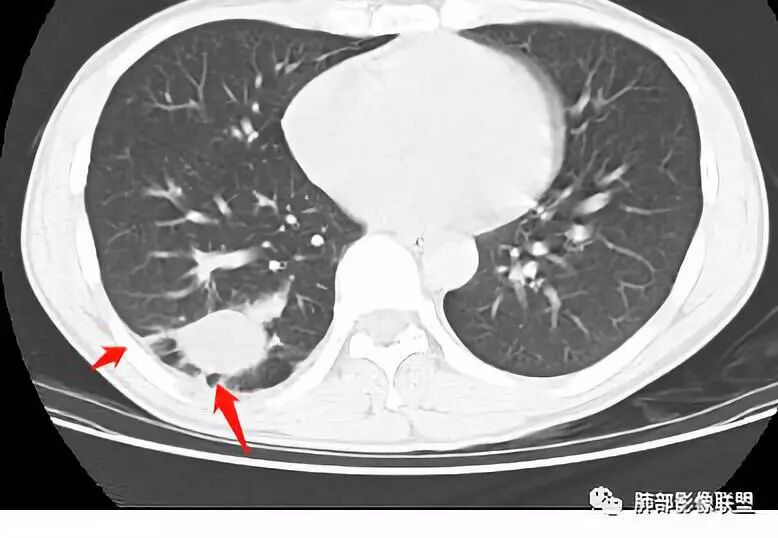

小赵:青年男性,慢性咳嗽,低热,血沉略快。右肺类圆形肿块,密度偏低,周围见条索,较低层面似见卫星灶,邻近胸膜增厚。增强扫描薄膜样强化。综合考虑结核可能

市医院-时建文:青年男性,慢性咳嗽,低热,右肺类圆形肿块,密度偏低,周围见条索,血管贴边,邻近胸膜增厚。结核?psp?

一米阳光:右肺下叶后基底段长圆形病变,边缘清晰,中心部密度减低,增强病变前缘见血管影,略环形强化,病变周围见点状及索条影,结合年轻病史,考虑结核

男,34岁,主诉:间断性咳嗽伴右胸反复不适半年;现病史:右胸不适,深呼吸加重,伴轻度咳嗽、低热;

青年男性、病史半年,低热;

右肺下叶囊性病变,边缘光滑,薄环状强化,内壁较光滑

血管贴边

周围多发长索条

远端有斑片状条带状高密度影,周围肺气肿

附近胸膜增厚,内有血管影